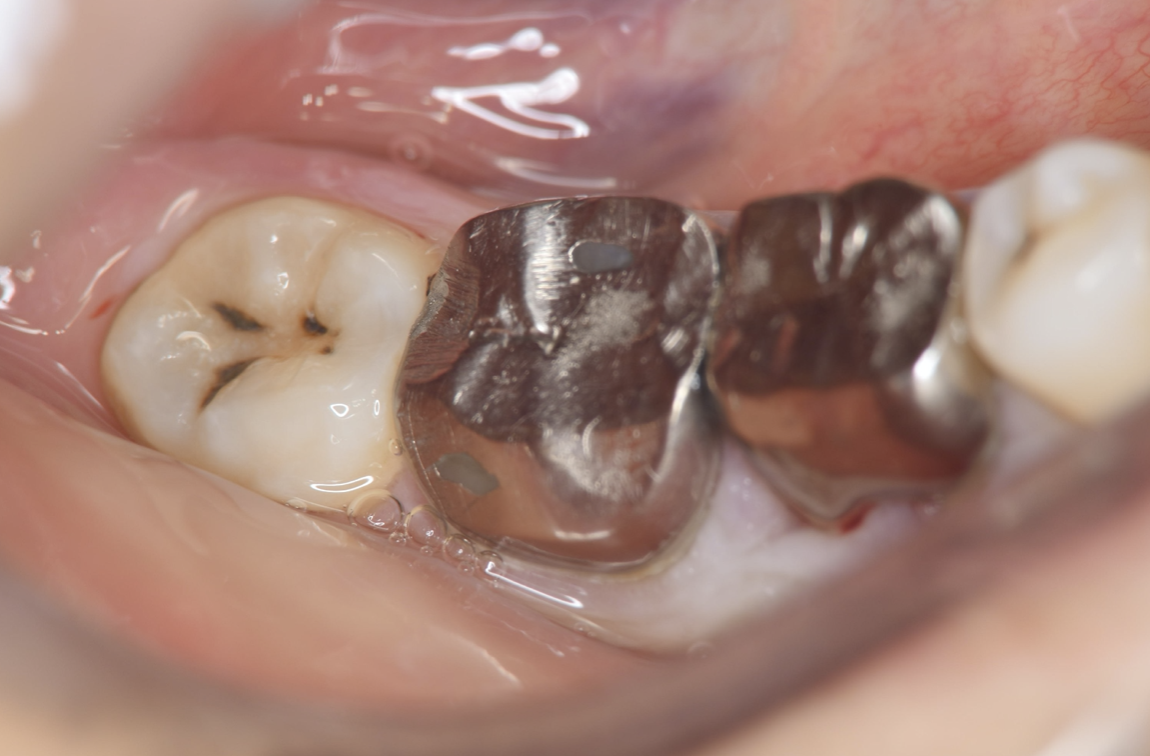

A 27-year-old female patient came to us with discomfort in the right lower jaw (Figure 1). Her primary symptoms were pain in the lower right tooth when biting and discomfort associated with not being able to chew well with the lower left single denture. The patient was married and had one young child, and previously received dental treatment in China, then had returned to Japan for childbirth and early childcare. The patient was a nonsmoker with moderate plaque control and medical history taking revealed no problems. In clinical and radiographic examinations, a root fracture was observed on tooth #46, which had been endodontic ally treated and restored with a full-cast metal crown. Periodontal probing revealed a pocket depth of 8 mm on the buccal center side of the tooth. No pain was detected with percussion and mobility of the tooth was normal. (Figure 1, Figure 2, Figure 3).

Figure 3.Preoperative intraoral findings. A metal crown was inserted at #46 and bleeding on probing during the periodontal pocket examination was noted.

Full metal crowns were inserted for #46 and #47. Pathological mobility and bleeding on probing were not seen, and the transplanted tooth showed good function.

Figure 7.Inter-oral photo obtained after treatment. Full metal crowns were inserted for #46, #47. Pathological mobility and bleeding on probing were not seen, and the transplanted tooth showed good function.